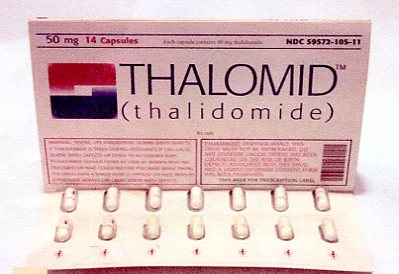

PHARMA PITCHES THALIDOMIDE FOR COVID![]()

JFK DOC SAVED BABIES FROM THALIDOMIDE